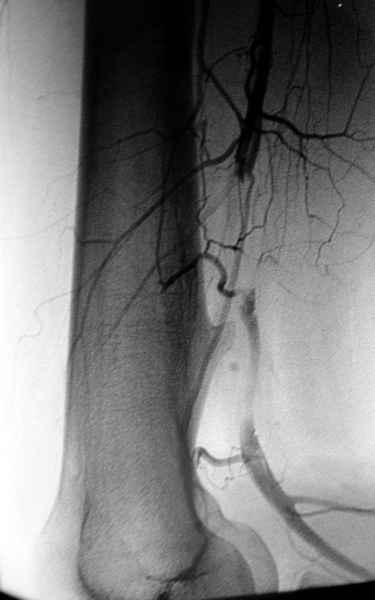

Обычная Solitary Osteochondroma или экзостоз относится к часто встречающимся доброкачественним опухолям. При давлении на нерв или на сосуды могут быть характерные симптомы, а так клинически не проявляется и обнаруживается случайно при исследованиях по другим поводам.

Пару лет назад наблюдал больную 35 лет, физически

здоровую, отслужила в Ираке, жаловалась на слабость в конечности во время физических нагрузок.

Ангиография подтвердила васкулярную аневризму в

результате давления экзостозом. Совместно с сосудистым хирургом была проведена плоскостная резекция с дальнейщим восстановлением сосуда венозным графтом.